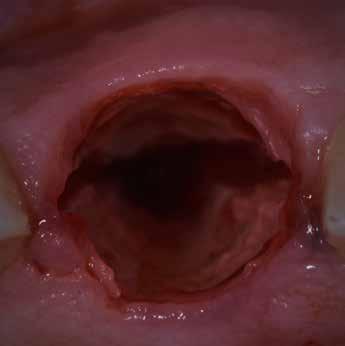

A korai harmicas éveiben járó hölgy rendelőnkbe érkezésének oka a jobb felső nagymetsző fog bizonytalan érzkenysége, elmondása alapján gyermekkorában trauma érte a felső frontrégiót. A frakturált klinikai koronákat kompozittöméssel helyreállították, egyéb kezelést akkor nem tartottak szükségesnek. Az utóbbi hónapokban tapasztalt érzékenység miatt kereste fel rendelőnket. A klinikai vizsgálat (1. és 2. kép) és a CBCT felvétel (3. kép) alapján diagnosztizált külső gyökérreszorpció megoldására a fog eltávolítását, implantátum

bukkális 1. kép: Kiindulási állapot, 2020. január. 3. kép: Kiindulási CBCT felvétel. 2. kép: Kiindulási állapot a palatinális oldal felől.